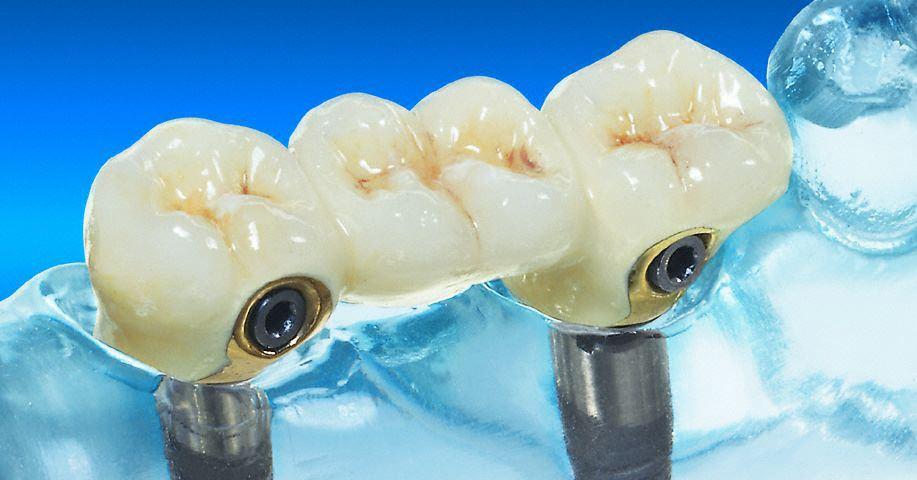

Freiendversorgung mit einem Implantat

Fehlt ein Zahn zur hinteren Begrenzung einer Lücke, übernimmt ein Implantat die Aufgabe eines Pfeilerzahnes zur Brückenversorgung. Die Kombination Krone/Implantat ermöglicht hier eine festsitzende Brücke und vermeidet eine herausnehmbare Prothese.

Feste Brücke im zahnlosen Kiefer

Bei ausreichender Knochenstärke können Implantate als Brückenpfeiler bis in den Molarbereich gesetzt werden. Bei weniger Knochen enden die Implantatpfeiler weiter vorn. Eine "Extensionsbrücke" ist die Alternative.